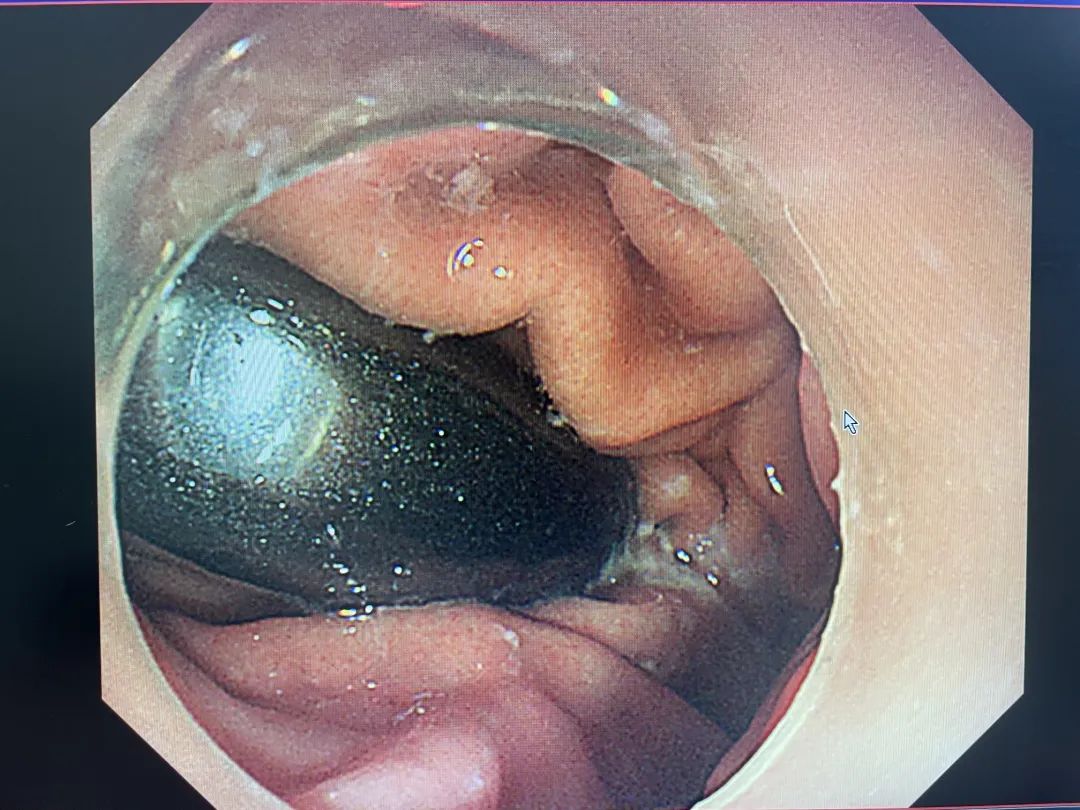

在胃镜的引导下,刘伟锋很快找到了异物。在发现异物表面光滑后,他特地选用了网兜型异物钳开展取出工作......20分钟后,异物被成功“网”出。经查,小明的食管无出血、穿孔等情况。

成功定位胃内异物

被网兜型异物钳“网”住的异物